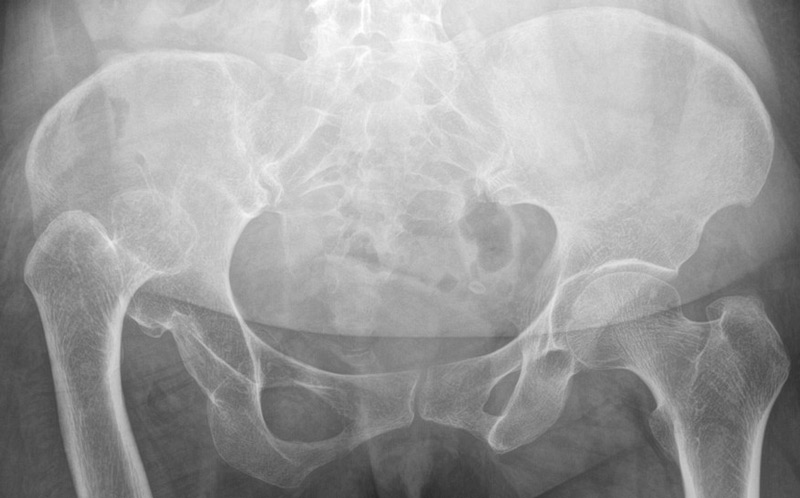

Pre-operative X-rays and CT-scan

Management of a hip dysplasia in a middle-aged woman:  Pre-operative X-rays and CT-scan

How would you grade this dysplasia?

• ✔️Crowe IV